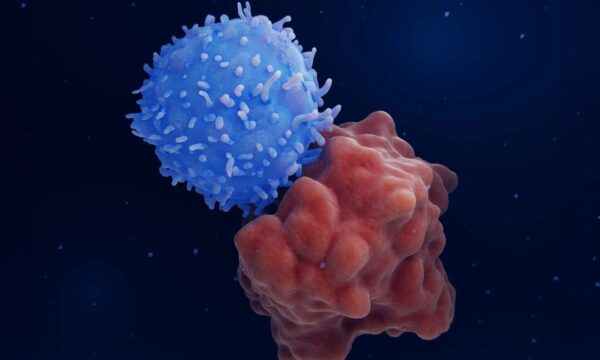

CAR-T細胞療法に関連する稀ながんで患者が死亡―リスクとは?

最先端のCAR-T細胞療法が稀な二次がんを引き起こすリスクについての最新報告。がん治療の新たな課題と今後の展望を詳しく解説します。